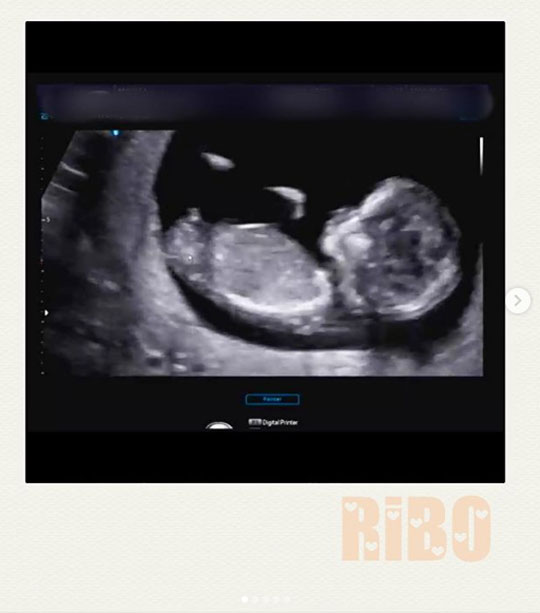

구재이는 22일 오후 자신의 인스타그램에 초음파 사진과 함께 “갑자기 찾아와 깜짝 놀라게한 리보”라며 아이의 태명을 소개했다. 이어 “아직은 모든 것이 낯설고 새롭고 놀라움의 연속이지만 건강하게 16주 차를 지나면서 잘 자라고 있어 감사한 마음뿐이다”라고 덧붙였다.

구재이는 “반가워 리보야”라고 덧붙이며 임신의 기쁨과 설렘을 다시 한번 만끽했다. 이에 팬들과 지인들은 축하 메시지를 전했다.

갑자기 찾아와 깜짝 놀래킨 리보

아직은 모든것이 낯설고 새롭고 놀라움의 연속이지만

건강하게 16주를 지나며 잘자라고 있어 감사한 마음뿐이네요.

반가워 리보야